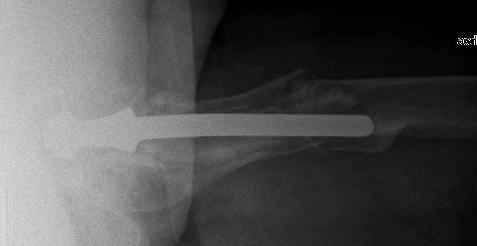

You transformed a cemented hip prosthesis to a cementless revision hip prosthesis with a little approach.

* your nail has a point of minus resistance at the tip of femural stem and at the fulcrum of the fracture; by the time could it break?

* by the time stem and nail could reciprocally move?

* distal fixation of the nail is based near only on two screws : are they sufficient to secure a good stability before fracture consolidation?

* materials of the stem and nail (I think Iron steel in both); if they should be different (and many hip prosthesis are made by an alloy that is not the same of the nails) we could see electrolytic phenomena

I generally should prefer a long stem revision prosthesis, as that allegated.

The nail tip is jammed. Since it is conical, it can only be jammed more with axial load.

I'd say yes because we use same 6 mm screws for femoral nailing and allow immediate weight-bearing regardless of fracture pattern.

The nail is Ti-based alloy.